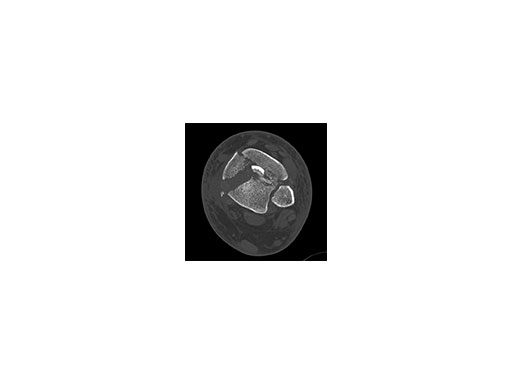

A 61-year-old laborer fell 5 meters from scaffolding. This was a closed injury with severe soft-tissue injury (Fig 67). He required three weeks of jointspanning external fixation prior to adequate resolution of edema.

Initial fixation was via a limited posteromedial exposure to buttress a posteromedial partial articular fragment (Fig 8). Following articular reduction and supplemental lateral column plate fixation via a limited anteromedial joint exposure, the VA-LCP Anteromedial Distal Tibia Plate was passed subcutaneous with subsequent percutaneous screw insertions into the plate shaft.